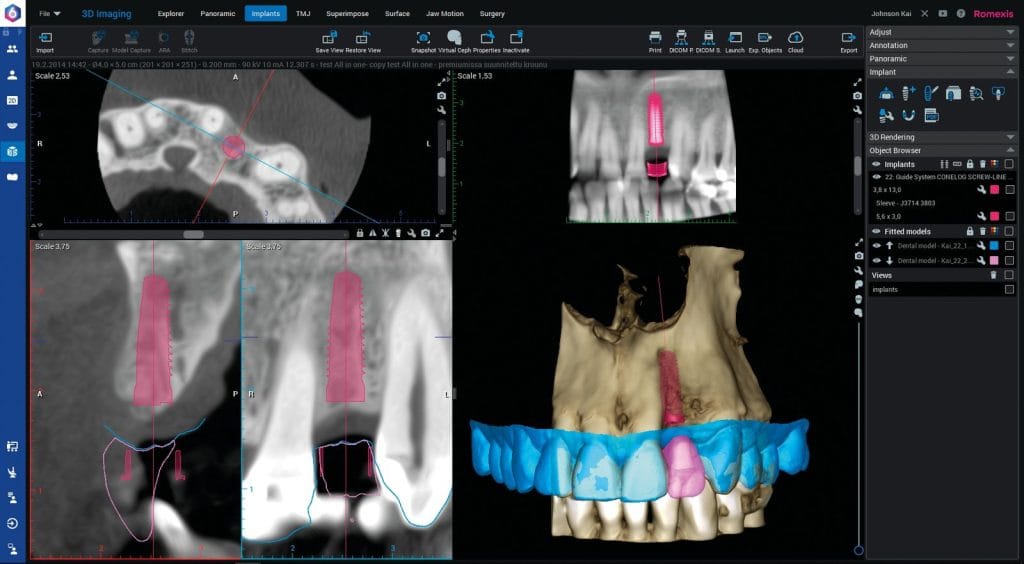

În timp ce pregătirea medicală este accesibilă prin nenumărate cursuri, în acest articol vreau să mă concentrez asupra avantajelor oferite de tomografia computerizată (CBCT). Vom vedea cum această tehnologie a devenit standardul de aur în implantologie, ce beneficii oferă pentru diagnostic și planificare și cum utilizarea inteligenței artificiale (AI) face posibilă o planificare automată și eficientă a tratamentului.

CBCT este, din punctul meu de vedere, soluția cheie pentru imagistica 3D în implantologie, oferind o perspectivă detaliată și precisă asupra anatomiei pacientului. În comparație cu radiografiile 2D:

Implantologia modernă nu se rezumă doar la plasarea implantului, ci și la integrarea acestuia cu structura osoasă și viitoarea restaurare protetică. CBCT-ul reprezintă baza chirurgiei ghidate, permițând planificarea virtuală a intervenției înainte ca pacientul să se așeze pe scaunul stomatologic. Cu ajutorul AI, unele cazuri pot fi pre-planificate automat:

- Ghiduri chirurgicale precise: Datele obținute prin CBCT și scanări intraorale permit crearea de ghiduri digitale pentru o plasare rapidă și exactă a implanturilor.

- Simplificarea prin AI: Algoritmii de inteligență artificială pot genera un plan preliminar pentru cazurile simple, reducând efortul medicului la verificare și ajustări finale.

Integrarea CBCT în cabinet face ca fiecare etapă — de la diagnostic la execuție — să fie sub control, oferind rezultate previzibile și de înaltă calitate.

De la simpla captare a imaginilor 3D pentru un diagnostic clar, până la planificarea avansată asistată de AI și chirurgia ghidată, CBCT redefinește standardele implantologiei moderne. Dacă îți dorești o practică mai sigură, mai eficientă și mai transparentă pentru pacienții tăi, CBCT este următorul pas firesc.